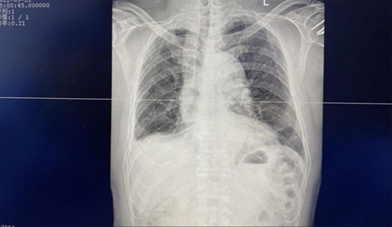

辅助检查:肋骨X片示:左侧第5、6后肋骨皮质不连续,肺野清晰,肋膈角锐利。

辅助检查:肋骨X片示:左胸肋5、6肋骨骨痂大部形成。